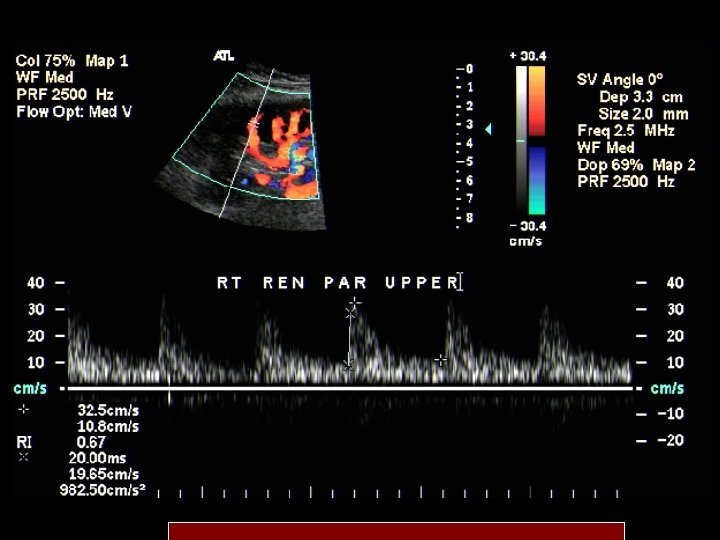

Increased velocities at mid renal artery segment: Typical of non-atherosclerotic RAS (such as FMD)